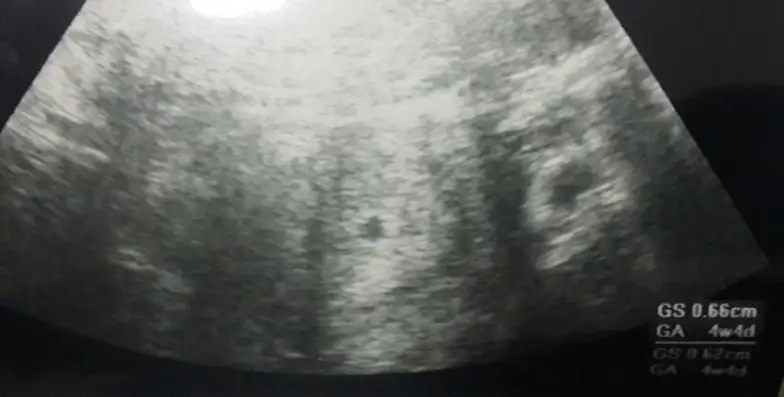

8 mart sali gunu yapilan ultrason bu cnm. Burda yazio 4+4 die

Eklentiler

• Screenshot_2016-03-08-22-53-53-1.webp

11,4 KB · Görüntüleme: 60